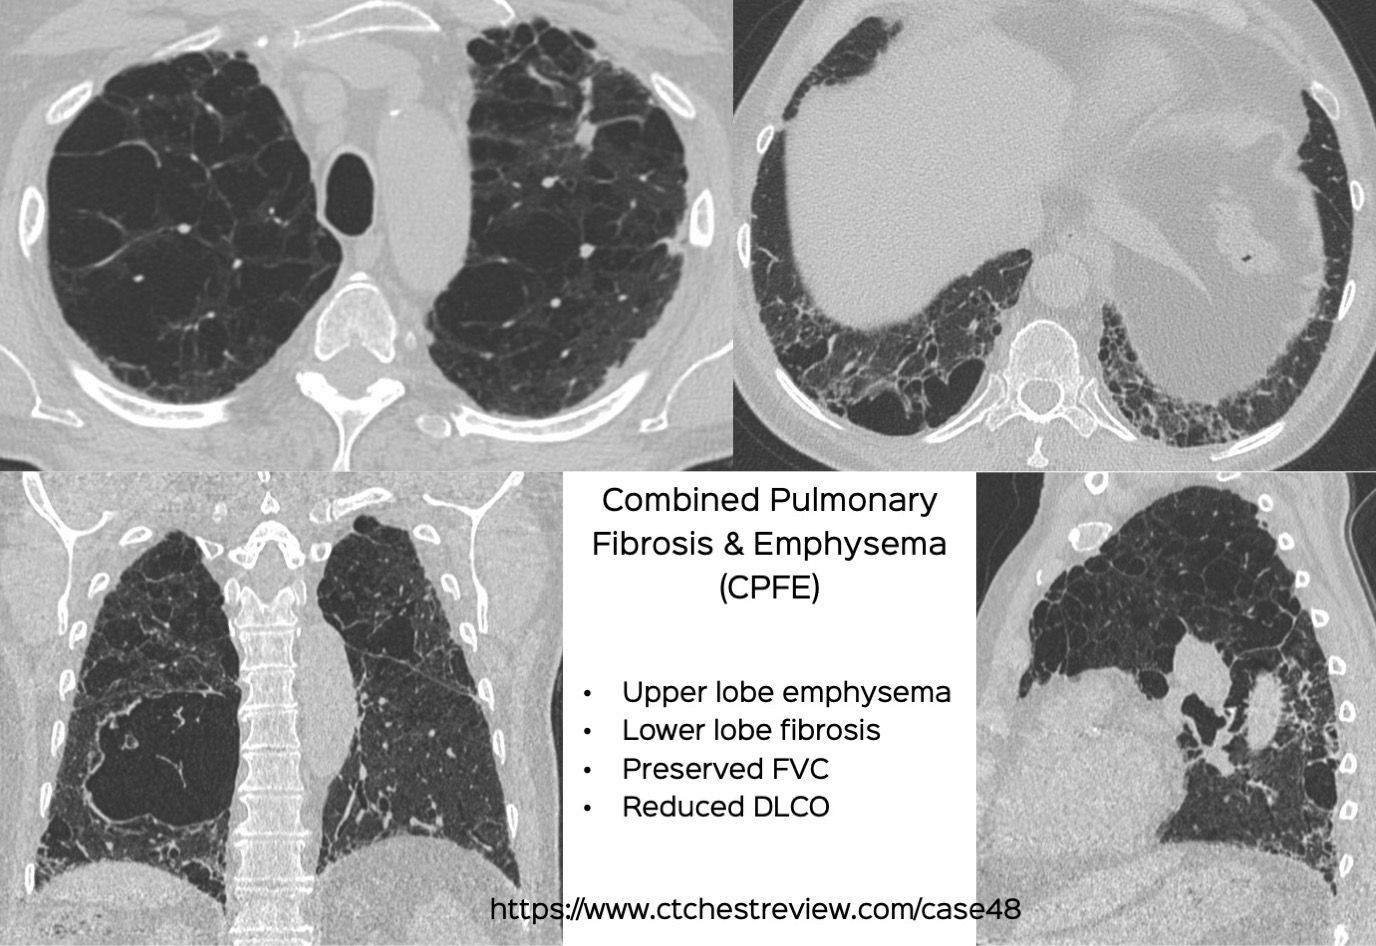

Case 48: Combined Pulmonary Fibrosis and Emphysema (CPFE) Members Public

CPFE is a distinct phenotype with upper lobe emphysema and lower lobe fibrosis, with preserved FVC and reduced DLCO